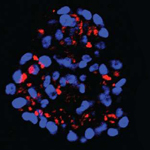

[16.09.2016] Острый лимфобластный лейкоз. Особенности роста раковых клеток

Группа ученых открыла новые перспективы в разработке эффективного лекарственного средства против агрессивной формы острого лимфобластного лейкоза (T-ALL). Был выявлен новый молекулярный механизм, который увеличивает жизнеспособность раковых Т-клеток и способствует их размножению.

Раковые клетки используют специальный сигнальный путь для поддержки интенсивного кислородного обмена и способности к делению. Сигнальный путь работает на основе белка ORP4L. Этот белок активно воспроизводится только раковыми Т-клетками и никогда не встречается в здоровых лейкоцитах